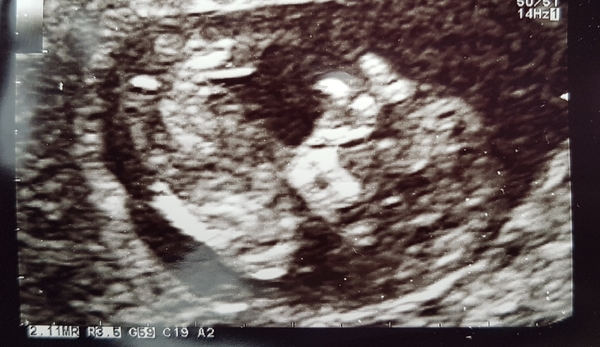

All good at the scan today. Measuring to dates as far as she could tell - it was being a pickle and kept curling up and turning it's back. Been discharged from the recurrent miscarriage clinic to normal ante natal care - bring on the 12 week scan next Wednesday!